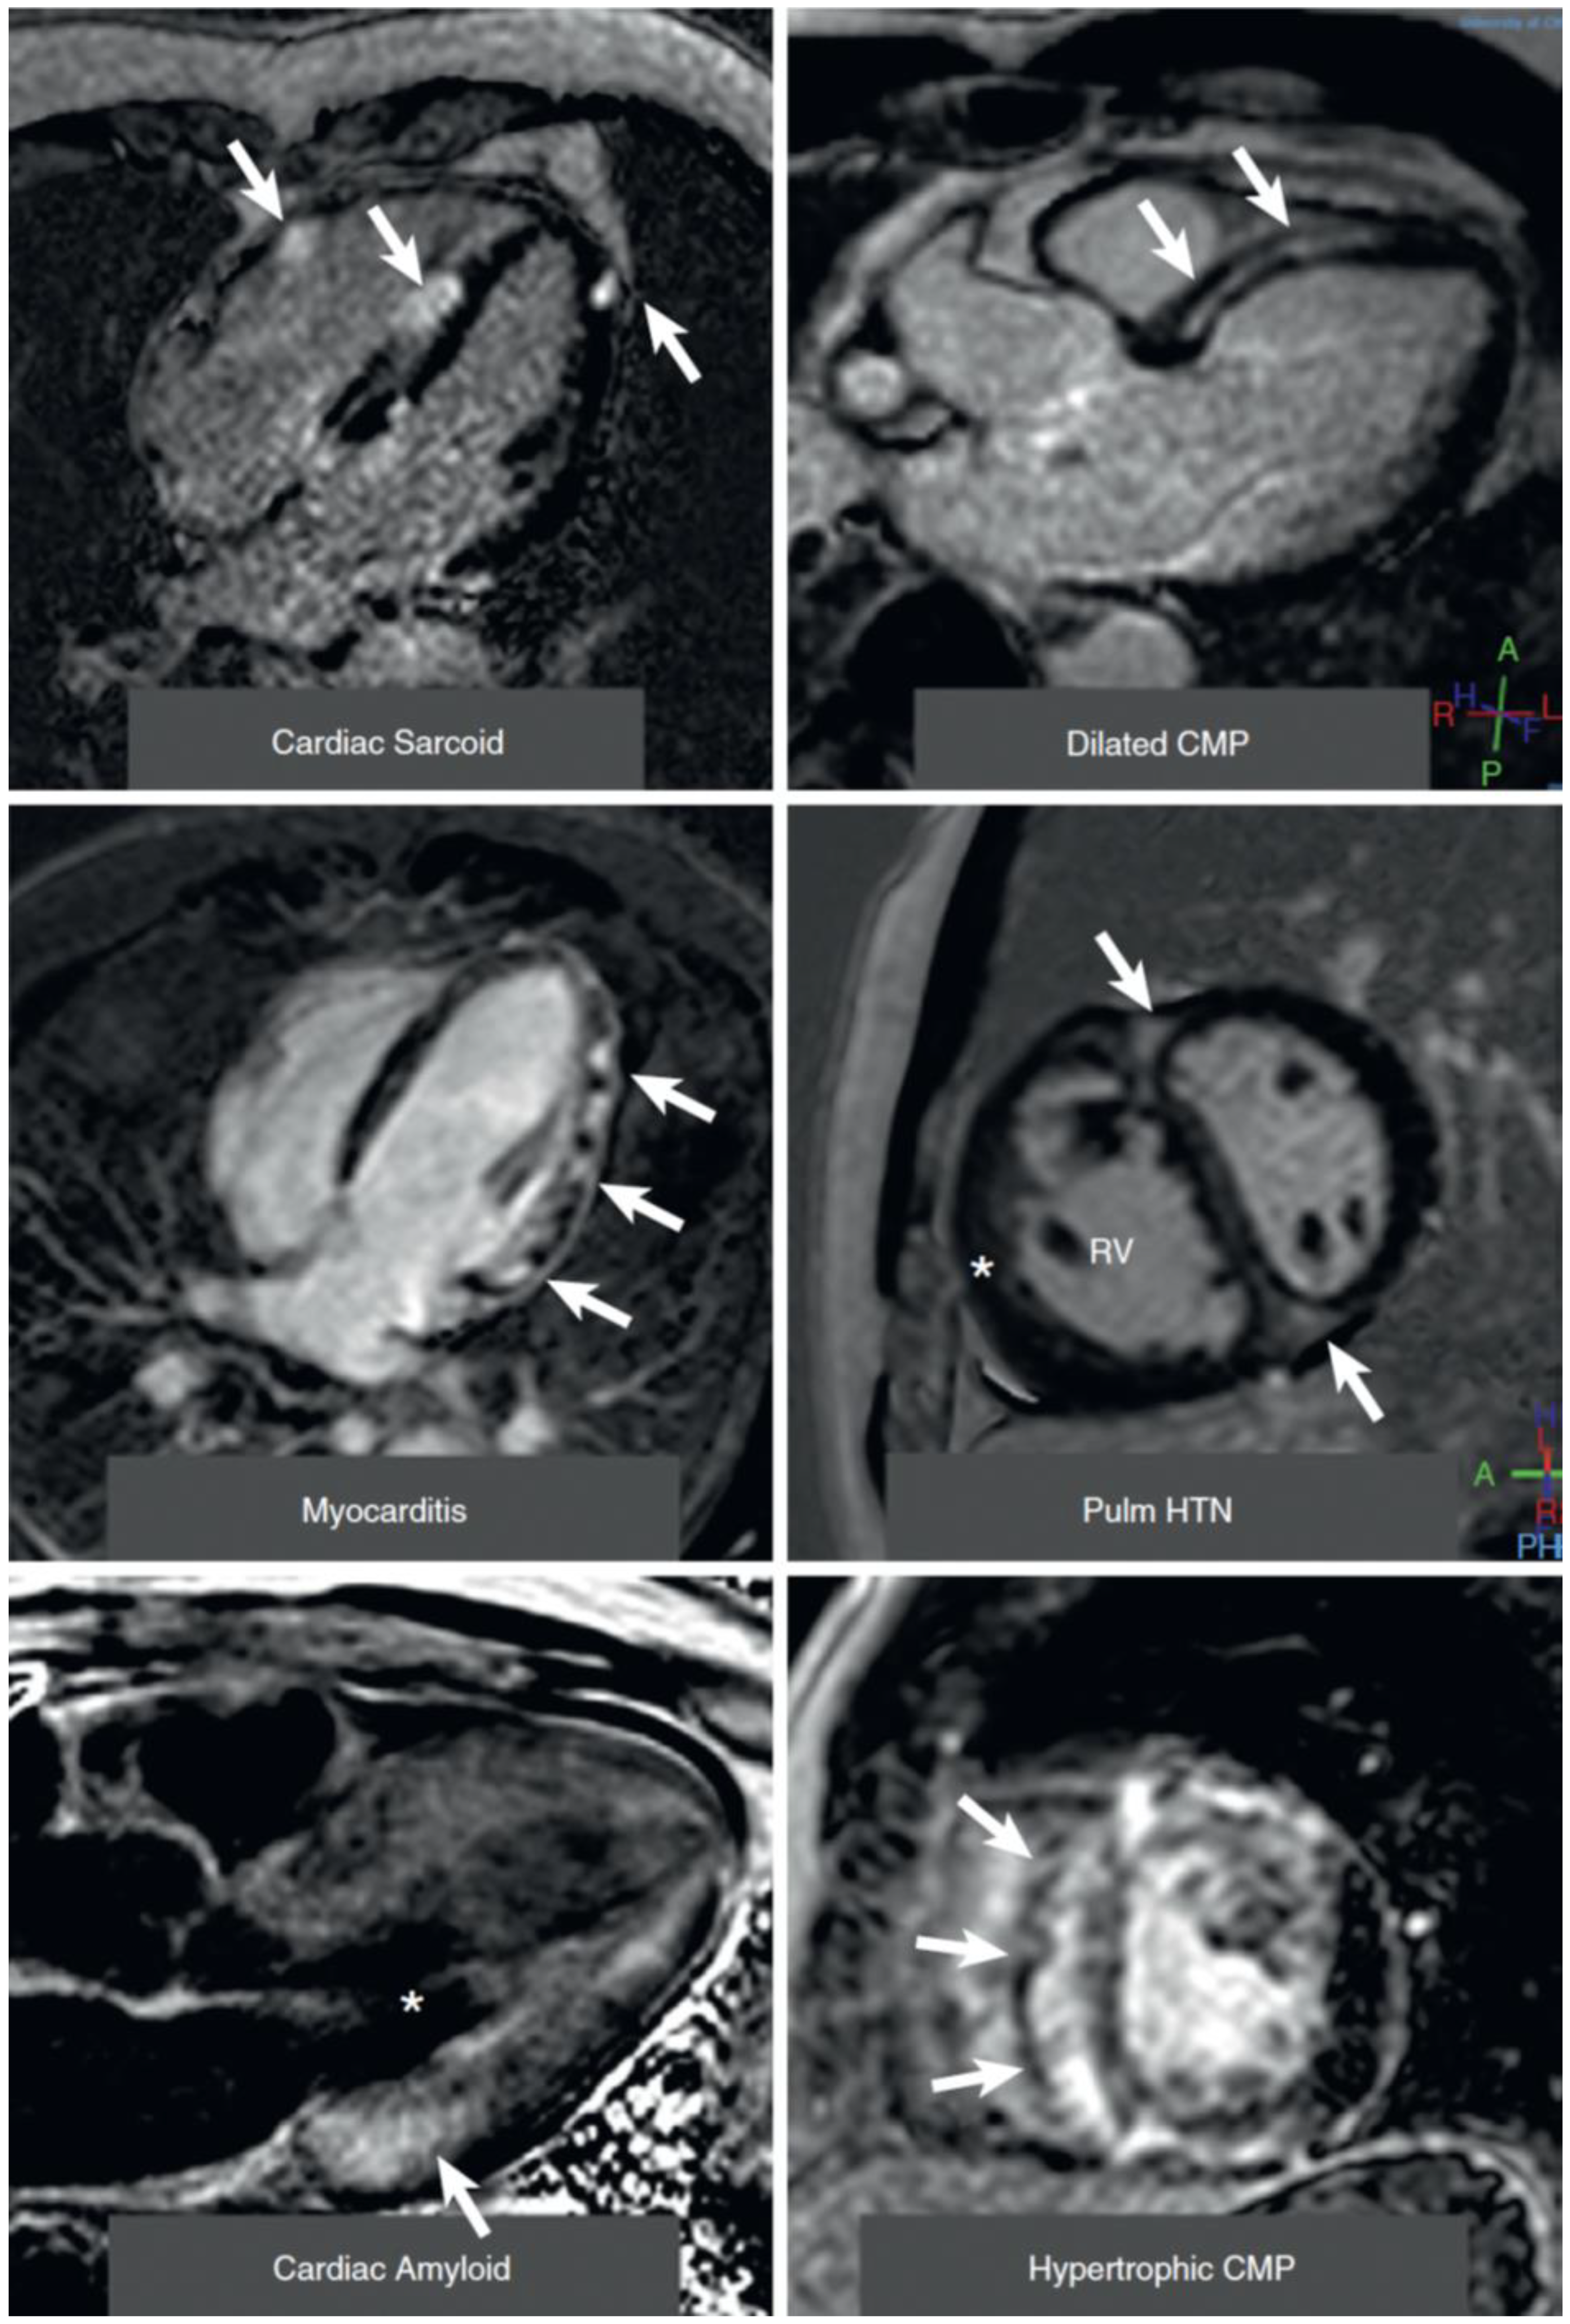

- Early and late tissue enhancement after contrast (gadolinium) application allows separation of intact myocardium from extracellular space, since intact myocardiocytes do not allow the intracellular accumulation of gadolinium. Thus, late gadolinium enhancement can detect myocardial scars as locally increased extracellular volume, such as infarcts, post-myocarditis damage, sarcoidosis, and other localized increases of extracellular volume (Figure 4). This technique relies on relative contrast intensity differences between myocardial regions, as in a myocardial infarction, but does not work in the presence of diffuse alterations of extracellular space. Though all of the cited etiologies result in the formation of localized increases of extracellular volume, often the “gestalt” of such a region of late contrast enhancement suggests a specific etiology. For example, subendocardial or transmural late enhancement following the “wavefront phenomenon” of myocardial ischemia in a coronary perfusion territory is strongly suggestive of post-infarct scar, and mid-wall late enhancement, especially in the lateral wall, suggests post-myocarditis damage. Note that similar principles enable contrast-enhanced CT to diagnose localized increases in extracellular space [36] in a similar manner to CMR, although the achieved contrast between normal and diseased regions is weaker than with CMR techniques.